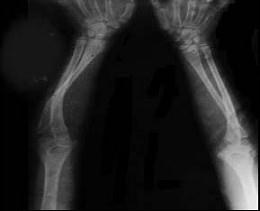

问题 女,2岁,有蓝色巩膜、听力障碍,四肢畸形等,请结合所提供图像,选择最佳选项 ( )

选项 A、呆小病 B、成骨不全 C、坏血病 D、软骨发育不全 E、佝偻病

答案 B